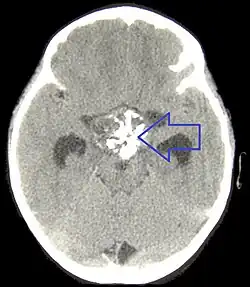

Das Kraniopharyngeom (zusammengesetzt aus lat. cranium = der Schädel, griech. pharynx = Schlund, „-om“ medizinisch Endung für Tumoren), nach dem erstbeschreibenden Pathologen Jakob Erdheim auch Erdheim-Tumor genannt, ist ein gutartiger Tumor, der durch eine Fehlbildung von Restgewebe im Bereich der Hirnanhangdrüse entsteht, der sogenannten Rachendachhypophyse. Diese Bildung des Restgewebes entsteht bereits embryonal, d. h. noch vor der Geburt. Die Gründe für diese Störung sind bislang nicht bekannt. Der auf kernspintomographischen Bildern sichtbare benigne (gutartige), evtl. zystische Tumor entsteht aus Resten der Rathke-Tasche, aus der der Vorderlappen der Hirnanhangdrüse während der Schwangerschaft entstanden ist. Der Tumor liegt deshalb im Bereich der Hirnanhangsdrüse.